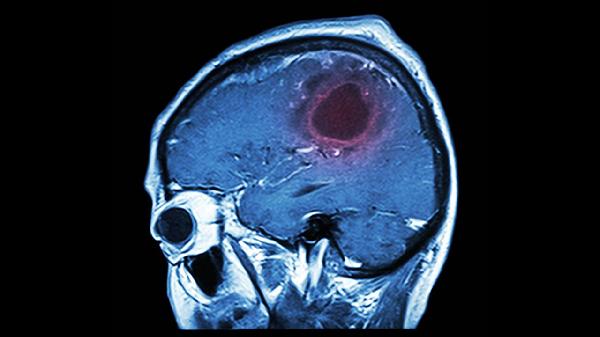

1、缺血性脑卒中

天丹通络胶囊可辅助治疗动脉粥样硬化性血栓性脑梗死恢复期。该疾病多与高血压、糖尿病等基础病导致血管内皮损伤有关,患者可能出现肢体运动障碍、感觉异常等。用药需配合阿司匹林肠溶片、硫酸氢氯吡格雷片等抗血小板聚集药物。

2、出血性脑卒中

对于脑出血后血肿吸收期的患者,该药能促进瘀血消散。常见病因包括长期高血压导致的血管破裂,症状可见意识障碍、头痛呕吐等。使用时应严格把握用药时机,避免在急性出血期应用。